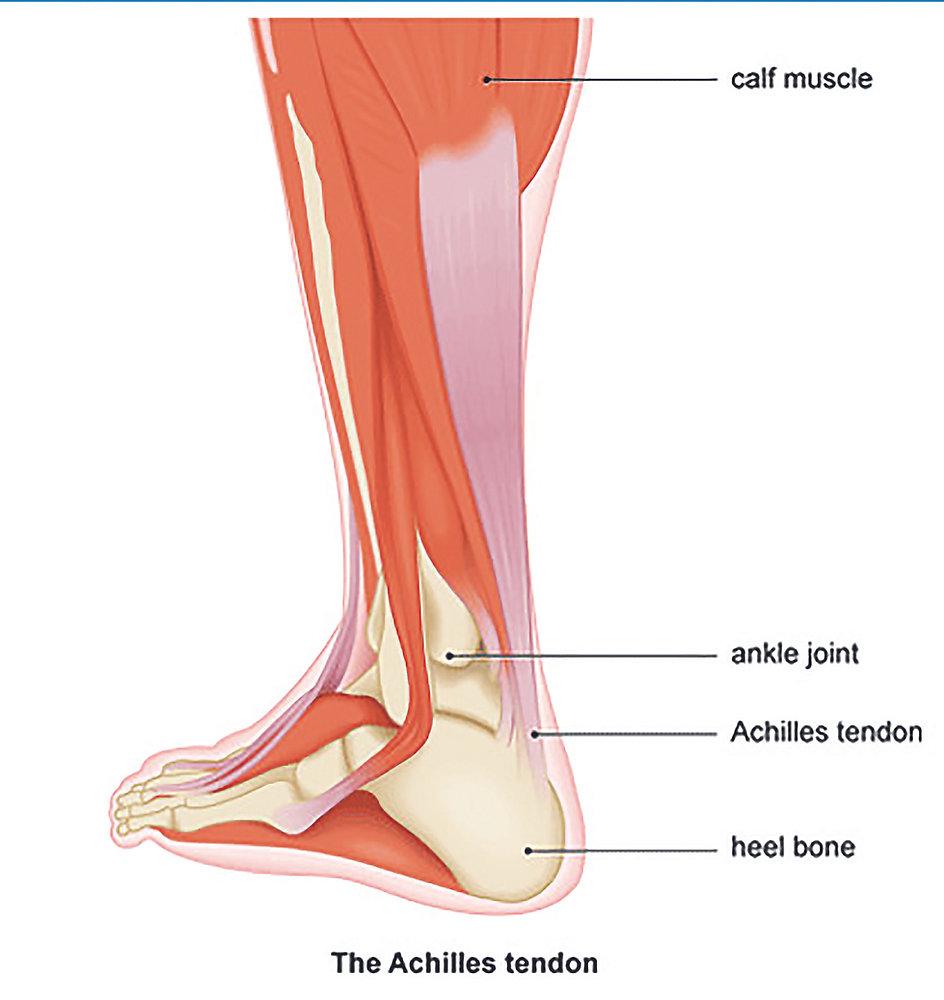

樂生療養院骨科主任兼副院長周禮智解釋,阿基里斯腱(Achilles tendon),又稱跟腱。由腓腸肌和比目魚肌融合形成的跟腱,以螺旋形排列方式連接跟骨後側,是人體中最大的肌腱。小腿後肌與跟腱一起負責足踝關節蹠屈的動作,幫助我們腳板往下踩,提供行走、跑步、跳躍時,往前往上的力量。

由腓腸肌和比目魚肌融合形成的跟腱,以螺旋形排列方式連接跟骨後側,是人體中最大的肌腱。